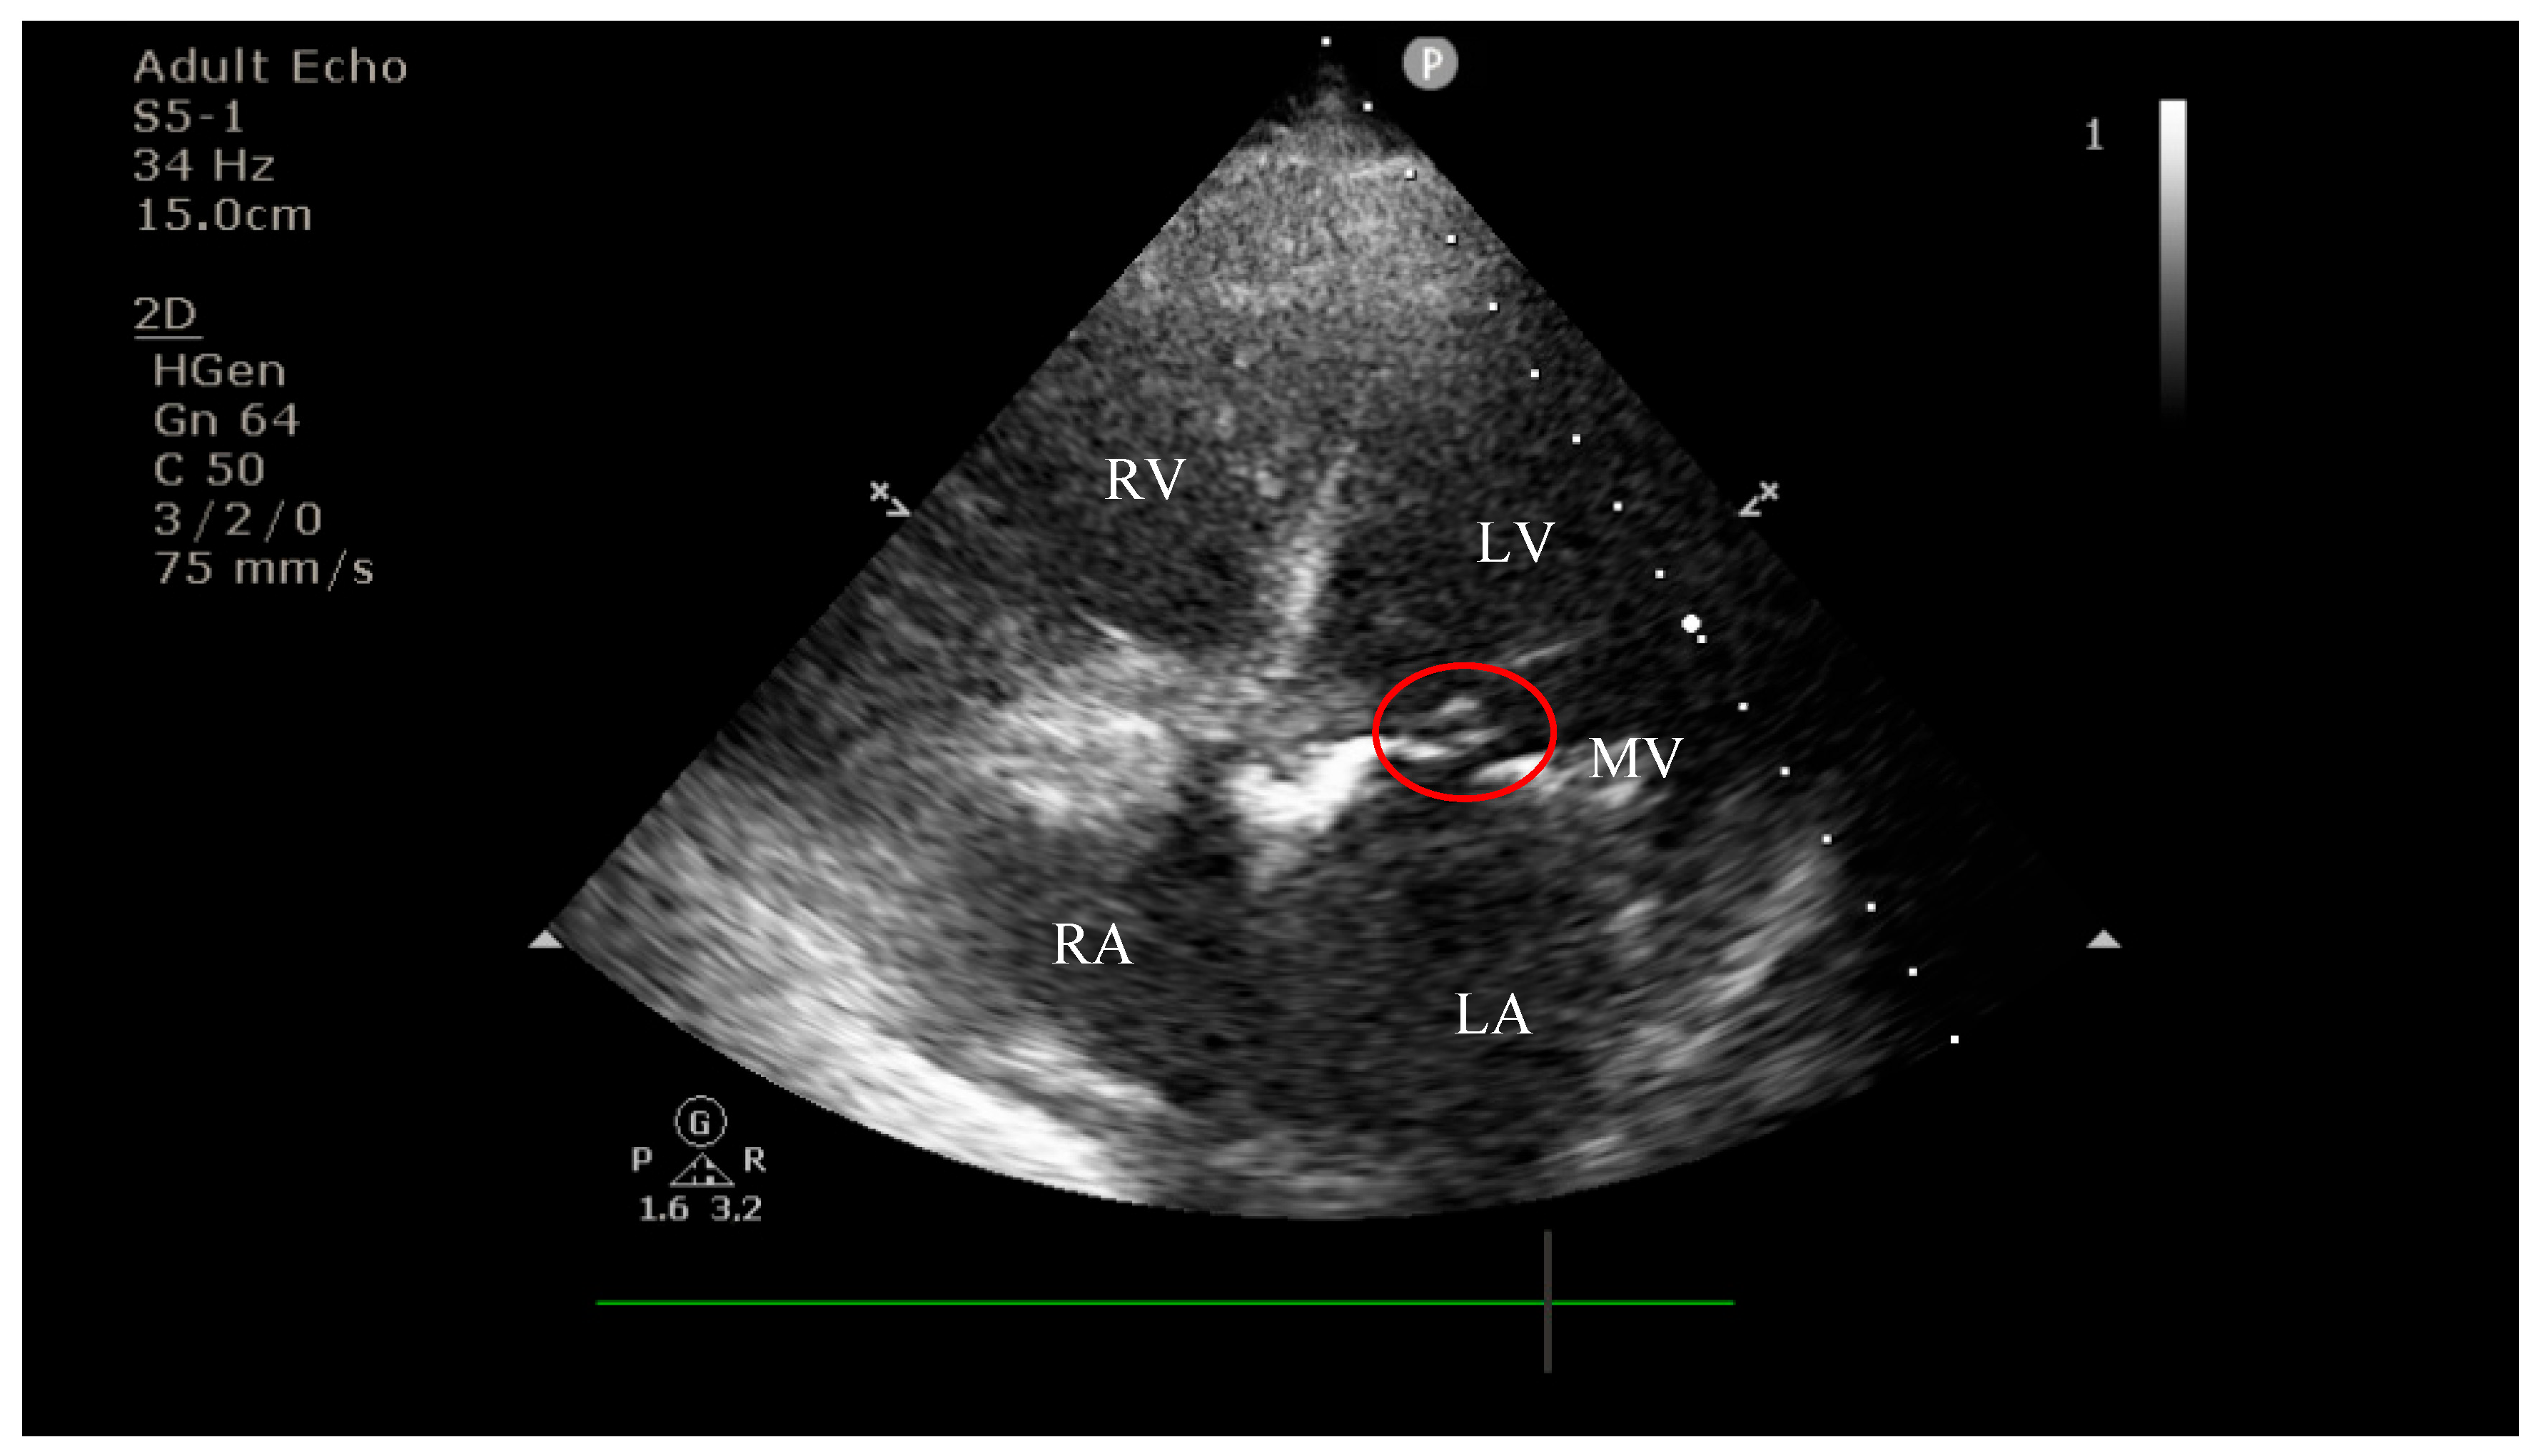

4.2. Diagnostic Findings: Mitral Valve Dysfunction and Embolic Phenomena

4.3. Coronary Complications and Diagnostic Dilemma